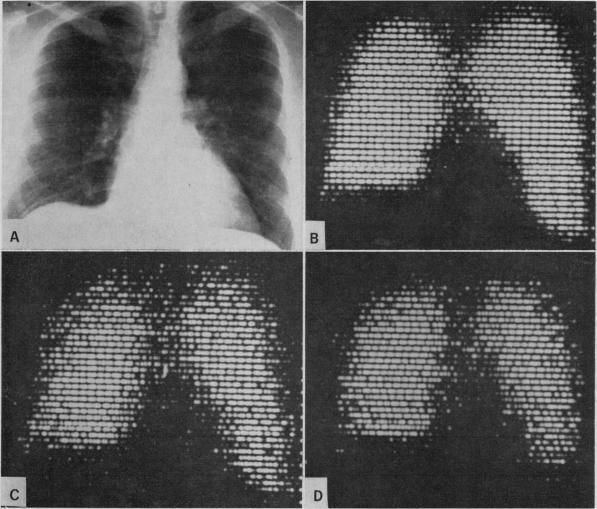

The measurement of ventilation-perfusion relationships using a multiple crystal rectilinear scanner.

Can Med Assoc J. 1968 Dec 14;99(23):1111-9.

THE DISTRIBUTION OF BLOOD AND GAS WITHIN THE LUNGS MEASURED BY SCANNING AFTER ADMINISTRATION OF 133XE.133氙注入后通过扫描测量肺内血液和气体的分布

A comparison of pulmonary angiography and intravenous radioactive albumin lung scanning in chronic obstructive pulmonary emphysema.慢性阻塞性肺气肿中肺血管造影与静脉注射放射性白蛋白肺扫描的比较。